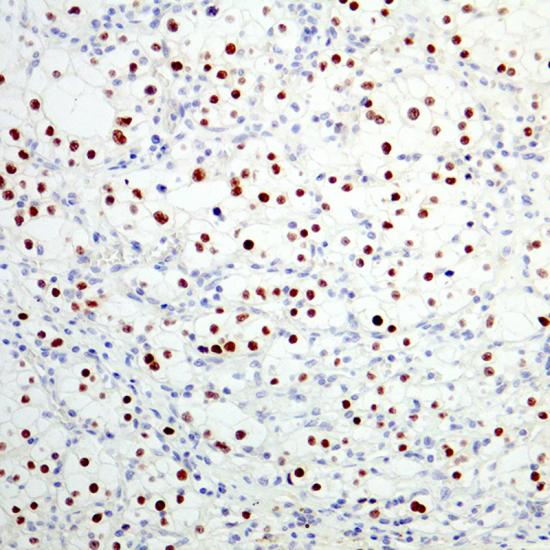

Pax-2

Pax-2抗體試劑(免疫組織化學(xué)) 閩廈械備20180284號(hào)

• 陽(yáng)性部位:

細(xì)胞核

• 陽(yáng)性對(duì)照:

腎細(xì)胞癌

Pax-2基因是Pax家族9個(gè)成員之一,是唯一可在腎臟表達(dá),又和腎臟形態(tài)發(fā)生密切相關(guān)的基因,主要參與早期腎臟足細(xì)

胞、腎小管上皮細(xì)胞分化的調(diào)控,對(duì)以后的內(nèi)皮細(xì)胞、系膜細(xì)胞的發(fā)育亦有引導(dǎo)作用。Pax-2是低級(jí)別的腎透明細(xì)胞癌的有用標(biāo)記物,研究表明在低級(jí)別的腎透明細(xì)胞癌中Pax-2表達(dá);而在高級(jí)別的腎透明細(xì)胞癌中,Pax-2 的表達(dá)降低或缺失。Pax-2 在絕大多數(shù)的腎乳頭狀細(xì)胞癌、嫌色細(xì)胞癌和嗜酸細(xì)胞瘤中不表達(dá)。